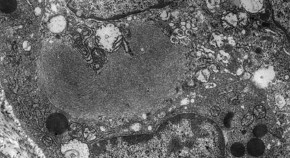

We optimized the sonoporation of a suspension culture with microbubbles for labeling and MR tracking of mesenchymal stem cells (MSCs). When water was used as the transmission medium between the acoustic probe and cell suspension, microbubbles gently collapsed with minimal cell damage. Under this condition, the number of labeled MSCs was 25%, which is 3.3-fold greater than the number of MSCs labeled using the conventional electroporation system, and the cell viability was maintained at approximately 80%. The MRI signal could be clearly observed for 2.0āĆā106 MSCs.